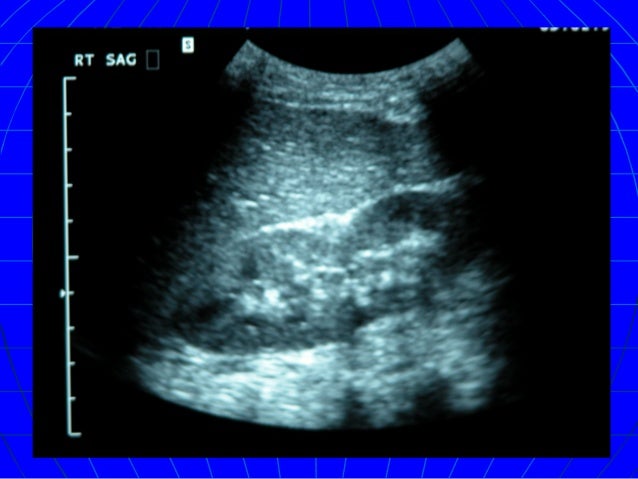

BLUNT ABDOMINAL TRAUMA/ HOW TO APPROACH ?